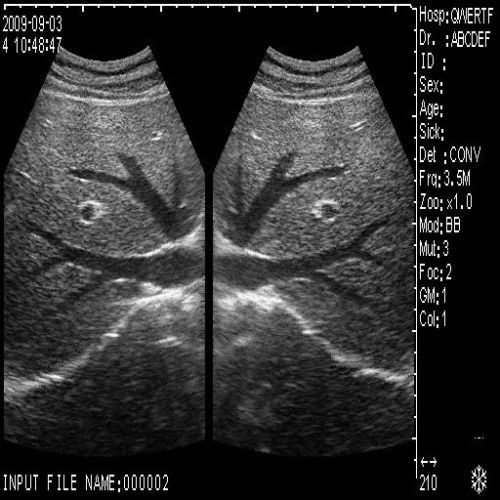

image: +3D High clear

Probe Function: 3.5MHZ convex, abdominal organs

The ultrasound scanner is a crucial tool in modern healthcare, particularly for monitoring pregnancy. Equipped with both convex and transvaginal probes, it provides exceptional 3D imaging capabilities. This means doctors can obtain clearer, more detailed images of the fetus, helping in making informed decisions regarding prenatal care. Because the images are so precise, healthcare providers can detect potential abnormalities early, enhancing the safety of both mother and child.